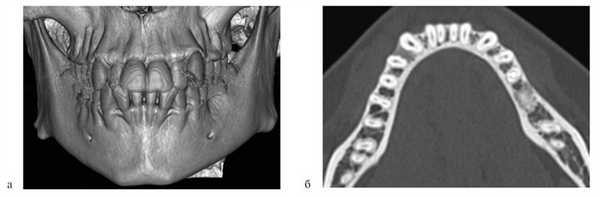

Деформации зубоальвеолярных дуг устраняли до проведения костной пластики. Для этого использовали аппараты, которые позволяли нормализовать положение резцов, фрагментов АО, положение резцовой кости и в результате создать зубоальвеолярную дугу правильной формы и определить истинный размер расщелины (рис. 2).

Рис. 2. Несъемный дуговой аппарат (система «2×4»). а — динамика перемещения зубов у пациента с ОРГН; б — динамика перемещения зубов у пациента с ДРГН.

При изучении диагностических моделей зубных рядов после ортодонтического лечения в 1-й группе зарегистрировали расширение верхнего зубного ряда в области клыков на 4,8 мм; длина переднего отдела этого зубного ряда увеличилась на 4,4 мм. Во 2-й и 3-й группах произошло расширение верхнечелюстной зубной дуги в области премоляров на 2,1 мм, в области моляров — на 2,3 мм; длина переднего отдела зубного ряда увеличилась на 2,7 мм.

Нормализовалось положение резцов у 68 (54%) пациентов, положение резцовой кости в сагиттальной и трансверсальной плоскостях — у 40 (40%). У всех пациентов при ортодонтической подготовке к костной аутопластике достигнуто расширение верхнего зубного ряда.